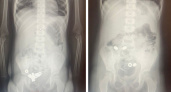

ВчераВ Воронежской больнице вылечили проглотившего шестнадцать гаек ребенка

В Воронежской больнице вылечили проглотившего шестнадцать гаек ребенка